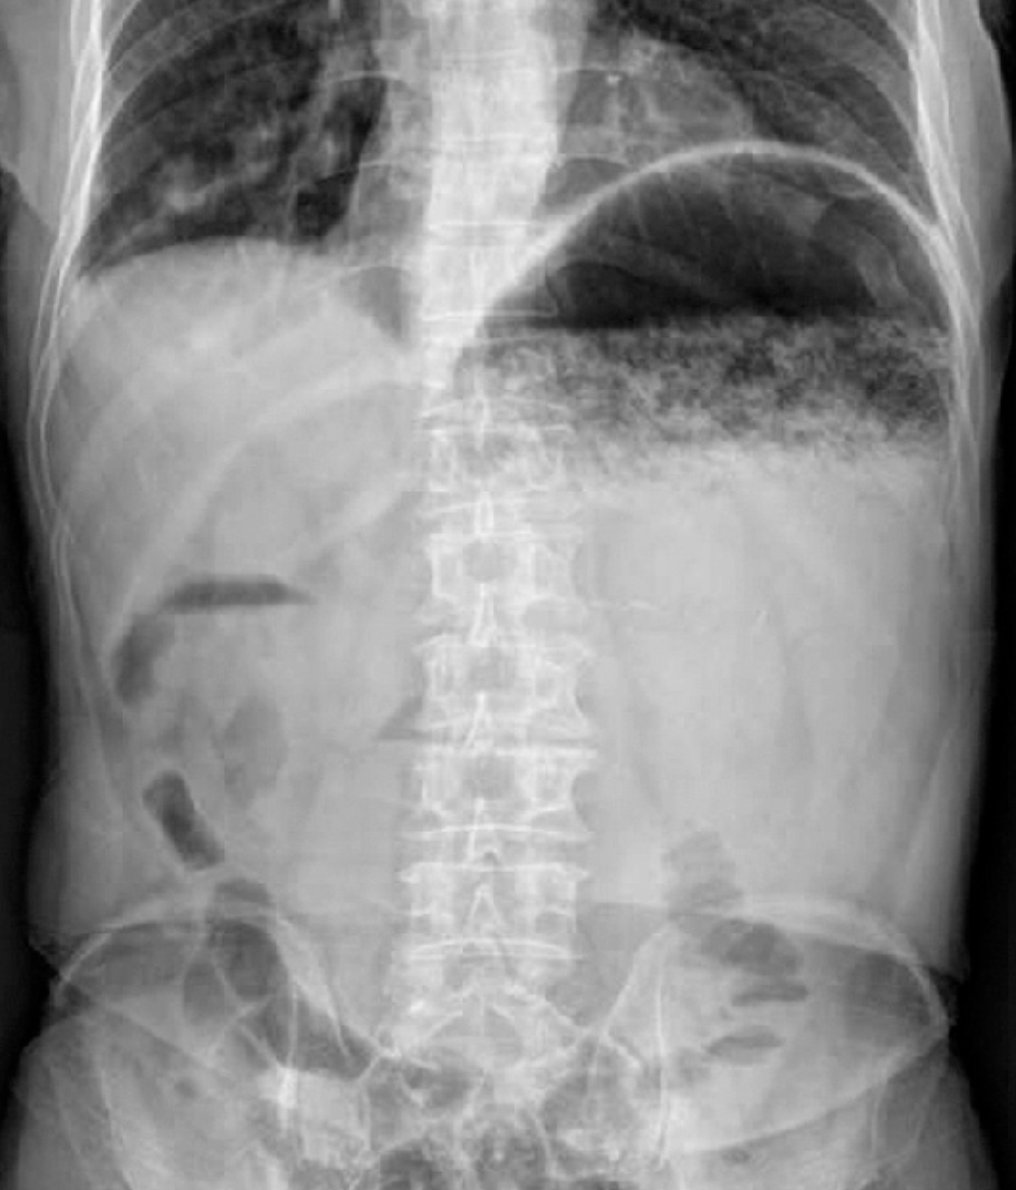

BOWEL OBSTRUCTION:

👉A bowel obstruction can either be a mechanical or functional obstruction of the intestines.

👉Obstruction frequently causes abdominal pain, nausea, vomiting, constipation, obstipation, and distention.

👉LBOs are less common and compromise only 10% to 15% of all intestinal obstructions.

👉Most common cause of all LBOs is adenocarcinoma, followed by diverticulitis and volvulus.

👉Colonic obstruction is most commonly seen in the sigmoid colon.

1/nImage